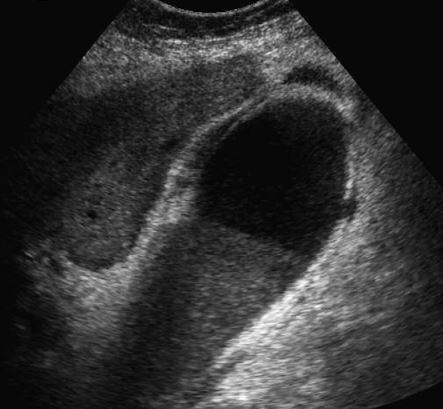

The gray-scale view shows a complex fluid

collection arising from the right kidney. In addition,

there is a simple-appearing, round, cystic structure

within the otherwise complex collection. The

power Doppler view shows flow in the apparent

cyst. All of these findings are consistent with a

pseudoaneurysm and adjacent hematoma.

Always put color Doppler on a “simple-appearing” cyst to make suer it is not something else!!!